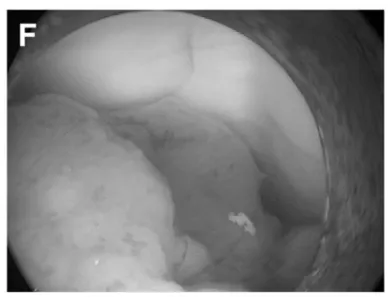

(F)第三脑室后部肿瘤